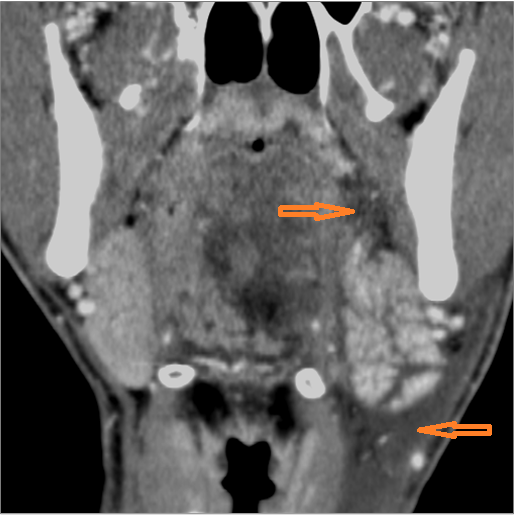

9 month old male presenting to the emergency room with poor feeding, fever, respiratory distress and possible retropharyngeal abscess or suppurative retropharyngeal adenitis.Exam

There is reactive retropharyngeal lymphadenopathy. |

There is suppurative retropharyngeal lymphadenopathy. |

Yes | NA |

If there is suppurative retropharyngeal adenopathy what is the maximum short axis dimension of the largest suppurative node. Measurement |

< 2cm | NA |

Pharyngitis with suppurative retropharyngeal adenitis.